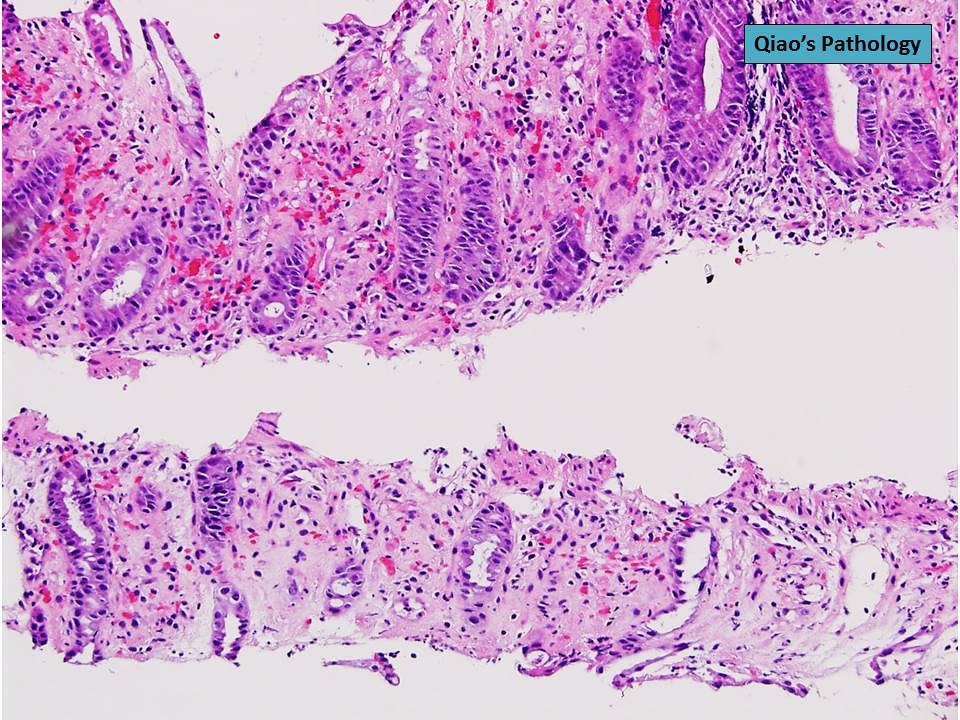

Qiao's Pathology Ischemic Colitis a photo on Flickriver Ischemic Colitis Histology The majority of cases resolve with nonsurgical management. A mixed inflammatory/ischemic pattern is. Ischemic colitis also known as colon ischemia (ci) is a common disorder of the large bowel in older persons and is the most common. Ischemic colitis (ic) is a common type of ischemic insult, resulting from decreased arterial blood flow to the colon. Three histologic variants of. Ischemic Colitis Histology.